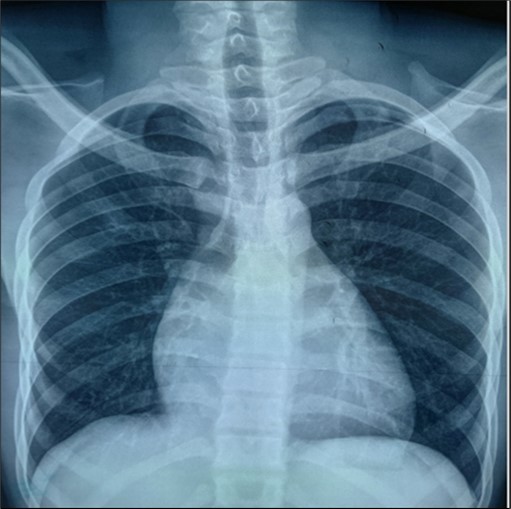

The frontal chest X-ray showed cardiomegaly with a cardiothoracic index of 0.7. The thoracic cavity and pulmonary parenchyma were without abnormality (Figure 1).

Figure 1.Frontal chest radiograph showing cardiomegaly

Cardiomegaly is frequent in Ebstein’s anomaly. A cardiothoracic ratio of at least 0.65 is associated with a poor prognosis 8 . This was the case with our patient.